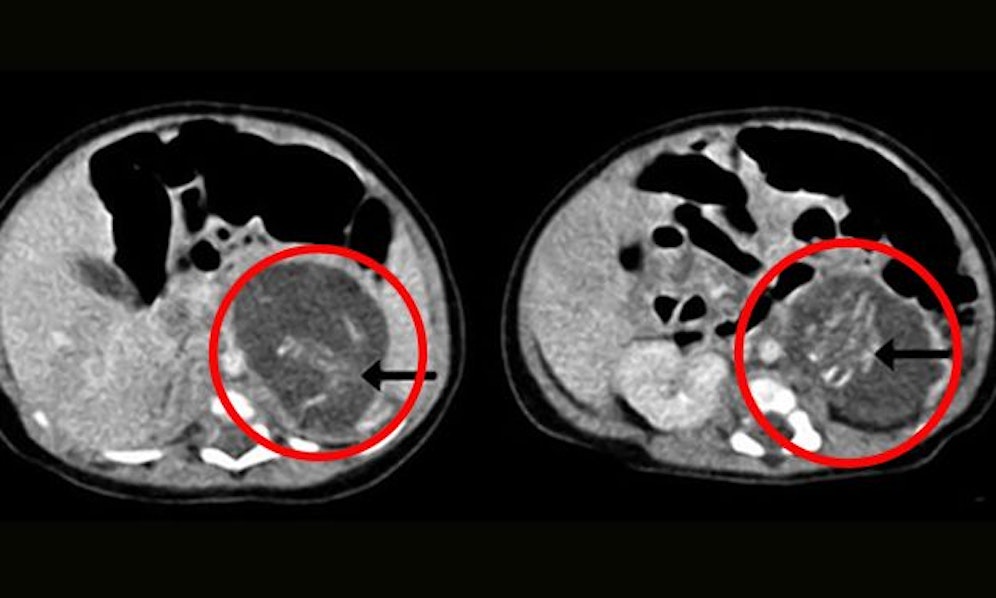

Bei dem Phänomen, das auch als "foetus in foeto" bezeichnet wird, entwickeln sich während der Schwangerschaft mehrere Föten, die dann von einem einverleibt werden. Der Umstand lässt sich pränatal nur schwer entdecken, daher entdeckten die Ärzte erst nach der Geburt des Kindes die anderen Föten im Bauch des Kindes.

Laut "mirrror.co.uk" hatten sie bereits Arme, Beine, eine Wirbelsäule, sowie Haut und Gedärme. Die Kinder waren ungefähr acht bis zehn Wochen alt.

Gebären konnte das Kind die Föten freilich nicht, sie wurden dem Mädchen wenige Tage nach der Geburt operativ entfernt.